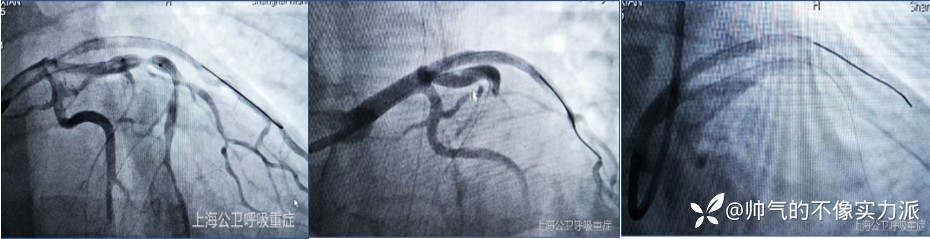

考虑冠心病、急性广泛前壁心肌梗死,心源性休克,溶栓后心电图仍存在ST段抬高,有PCI指征。ECMO支持下行冠脉造影见左前降支狭窄99%+冠脉支架置入,成功解除左前降支血管狭窄。

图4